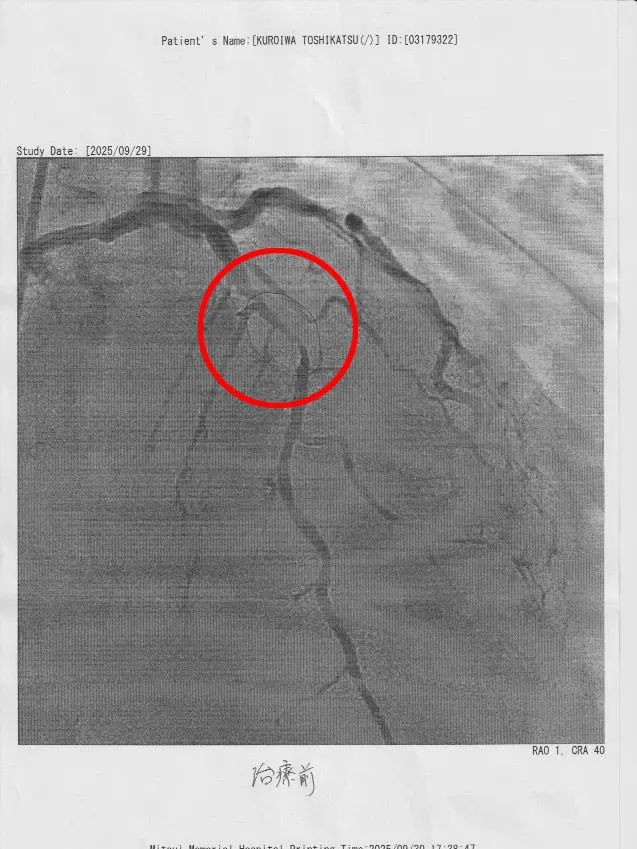

西村先生がどのようにステントを入れたかを、画像を見ながら説明してくれた。

太い動脈が詰まり、心筋梗塞の症状が出た。

そちらの部分はステント留置し治療を完了したとのこと。

しかし、もう1カ所(以前心筋梗塞になりステント留置してある場所の手前部分)に

かなり細い部分があり、

こちらを半年後の検査時に様子を見て処置するかもしれないとの事。

上の写真が治療前、中の写真が治療後、下の写真がもう1カ所の細い血管